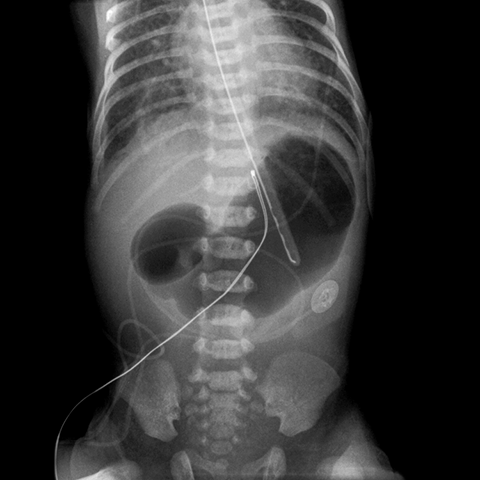

Duodenal Atresia